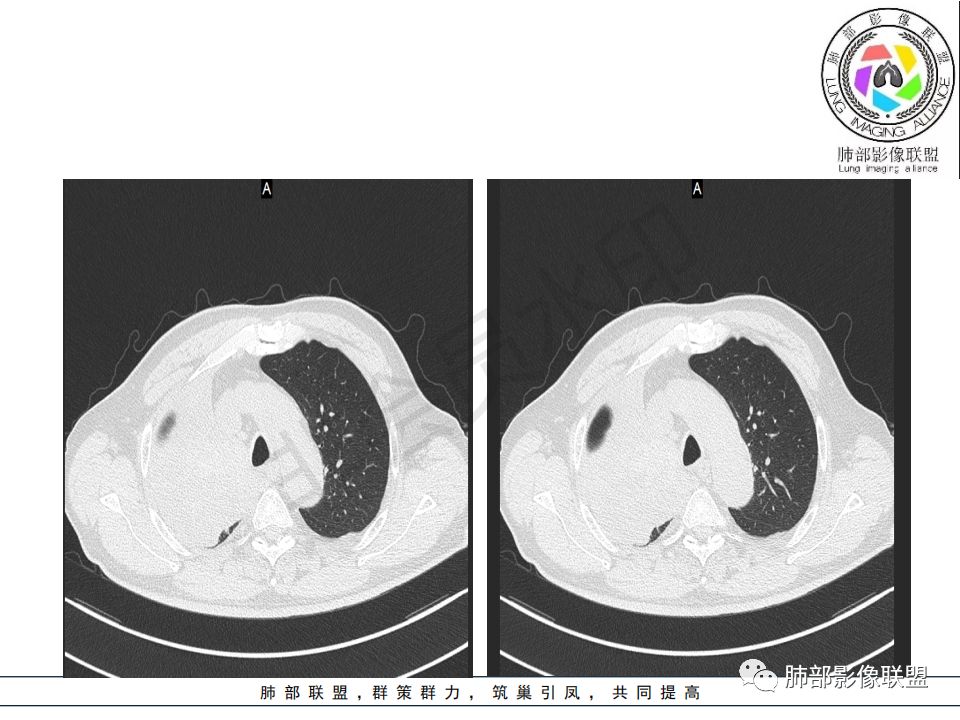

病史:男.77岁,咳嗽1月;干咳,少许白痰,无发热,2013胃癌术后,角蛋白24.65(0-3.07),SCC和proGRP不高;

影像:影像右侧大支气管阻塞,临床没有症状或很轻微,要想到胃腺癌转移;胸壁代偿好,透亮度稍低不明显,慢性过程;34.8-52.5HU,主病灶支气管前壁另有1结节,都做成增强两期了,动脉期较平扫有强化;

晨读:患者老年男性,以咳嗽一月就诊,少量白痰,胸CT:纵隔右移,右肺体积缩小,气管下段管壁可见结节样改变,气管软骨变形,气管下段及右主支气管可见新生物向管壁浸润,并向管腔外生长,右上肺肺不张,但不张边缘可见病灶呈膨胀性生长,可见分叶,增强后强化明显。考虑:肺部恶性病变(鳞癌?)

又是一个支气管腔内占位,按常规,右肺上叶支气管占位,突入腔内,上叶不张,恶性没问题,鳞癌可能,但这么大,坏死少,是个疑点

右肺上叶肿块,边缘光滑,略膨隆,近段支气管堵塞,平扫密度均匀,增强后不均匀强化,其内可见不规则血管和坏死,纵隔淋巴结肿大,老年男性,无感染性病史,综合考虑恶性肿瘤(鳞癌,腺癌),鉴别:OP(一般下叶多见)

晨读病例:老年男性,症状轻,右侧胸廓略塌陷,右肺主支气管内外软组织影,支气管变窄截断,右肺上叶不张,其内见细砂样钙化,周围看见小结节,右肺门看见一淋巴结稍大,增强不均匀强化,胃癌病史,常规考虑:转移,或原发肺恶性鳞癌。鉴别支气管TB?

从强化情况和冠状位看主要还是从外向内的一个肿块,有不张,但不张范围不大,近端支气管堵塞,考虑腺癌或类癌(原发或转移都可能),鉴别鳞癌。